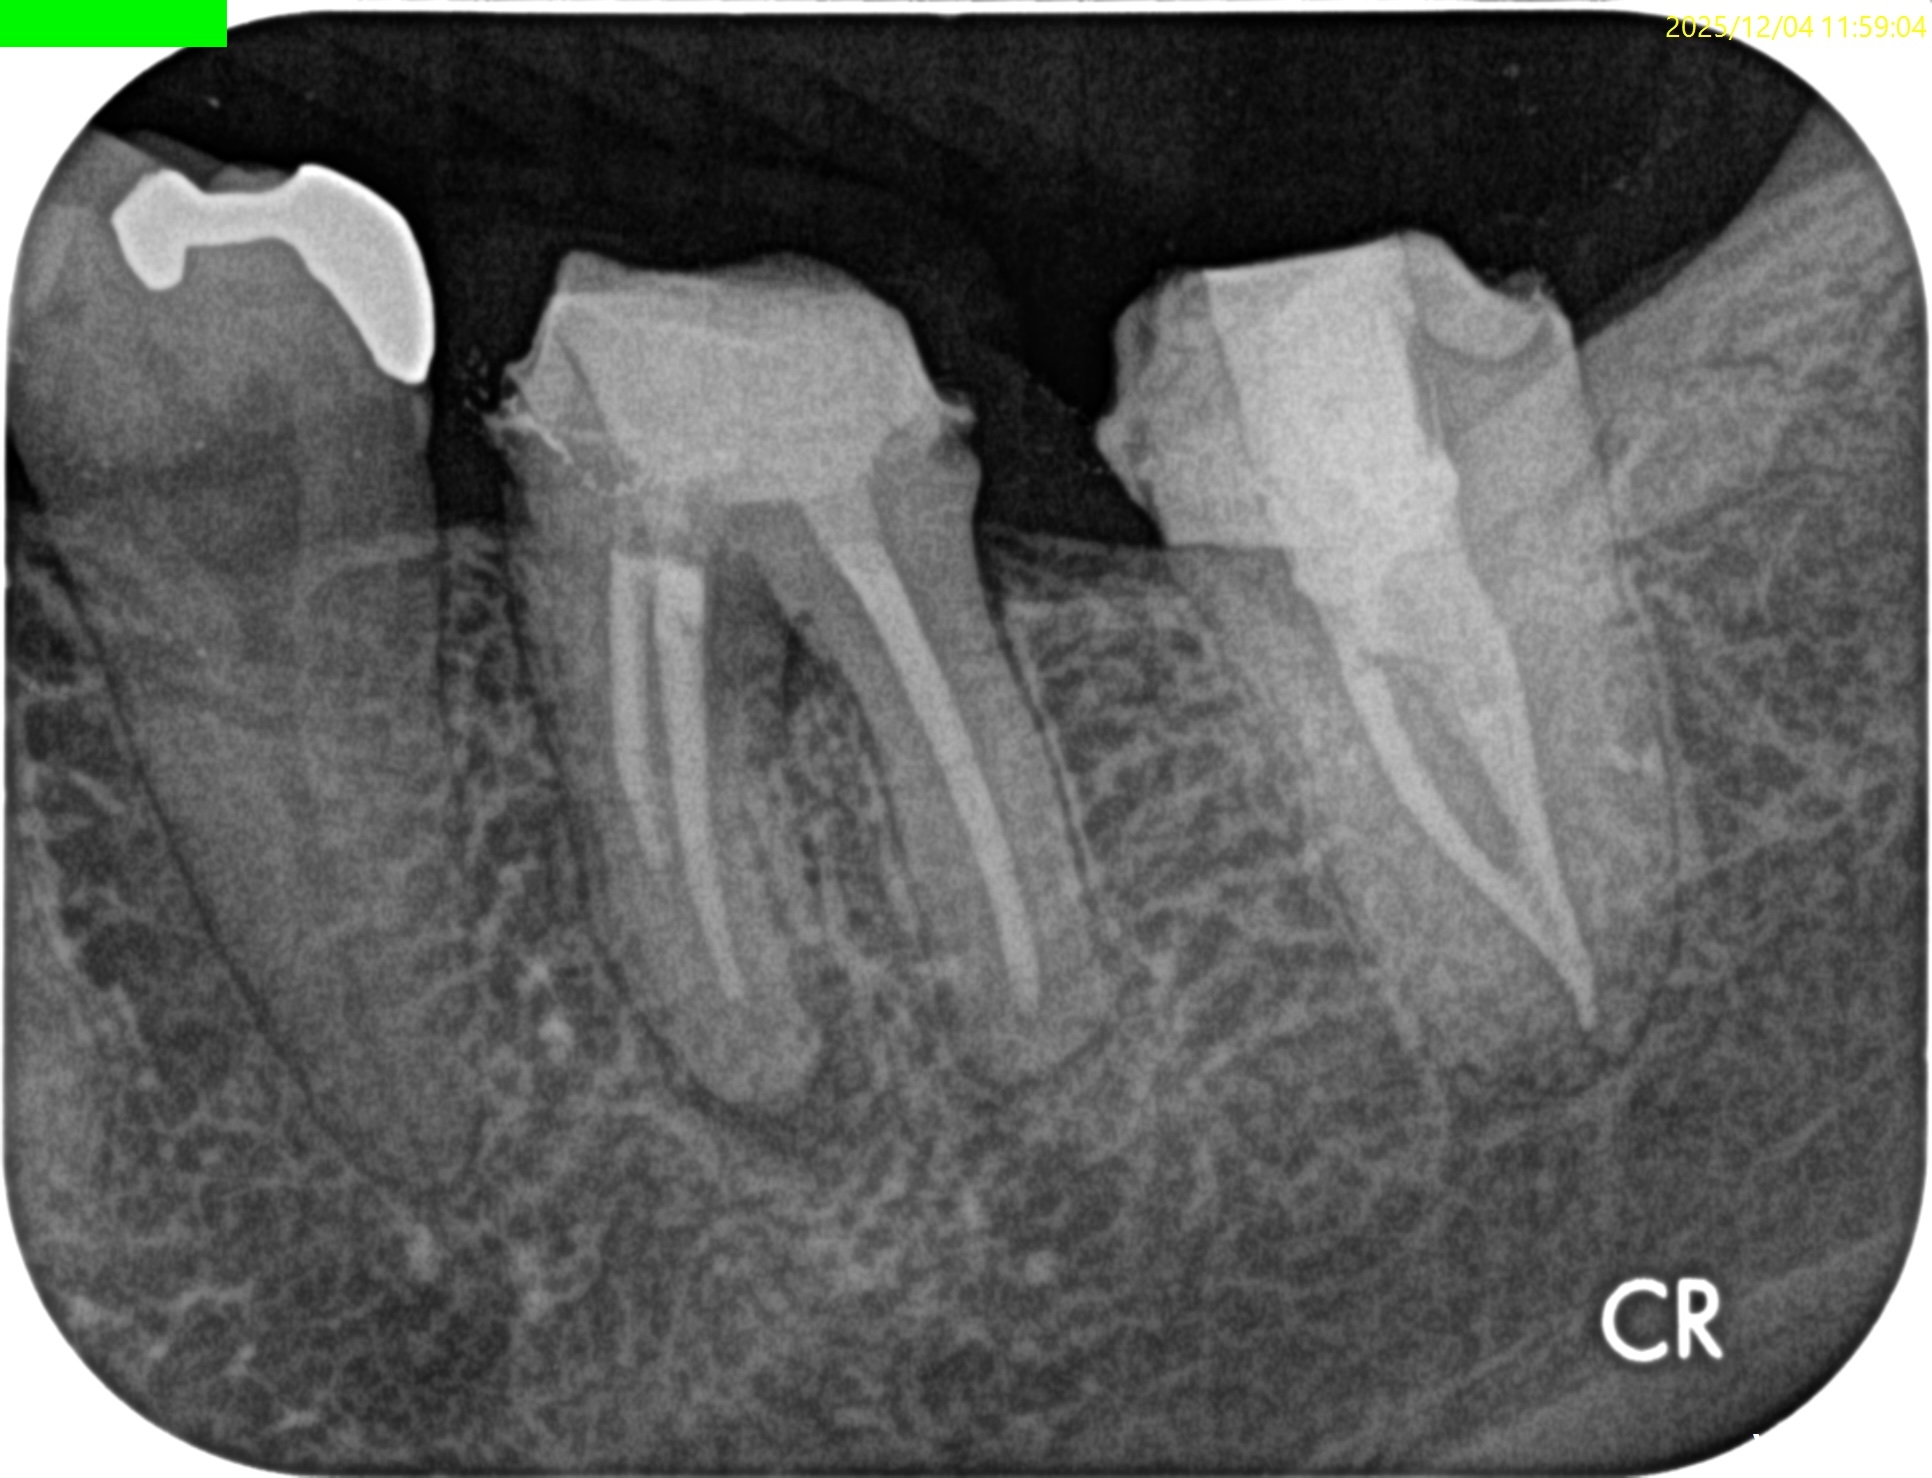

PA(2025.10.31)

PAでは上記の私の謎は解明できない。

#19の近心根には根尖病変は見えるが…

圧痛が強いのは#18近心だ。

意味がわからない。